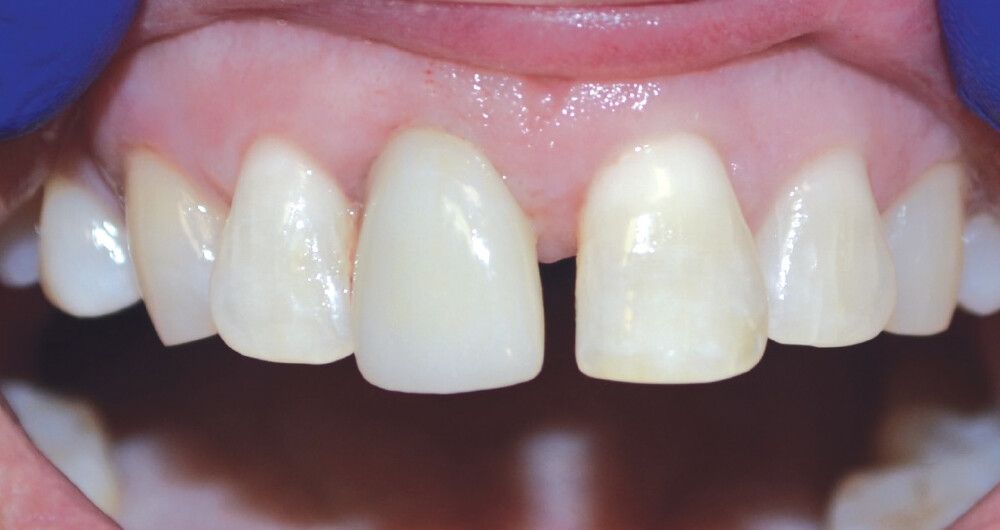

The patient presented with a failing tooth #8. After extraction, the socket shape resembled a triangle. Because of the round shape of the dental implant, there were gaps between the implant body and the alveolus which required grafting.

A temporary appliance was delivered and the site allowed to heal. After approximately three months, the healing abutment was removed and stability was checked with a Penguin RFA® A small amount of gingival recontouring was completed with a diode laser, and impressions were taken. The final BruxZir® Esthetic restoration was delivered, and final adjustments were made.